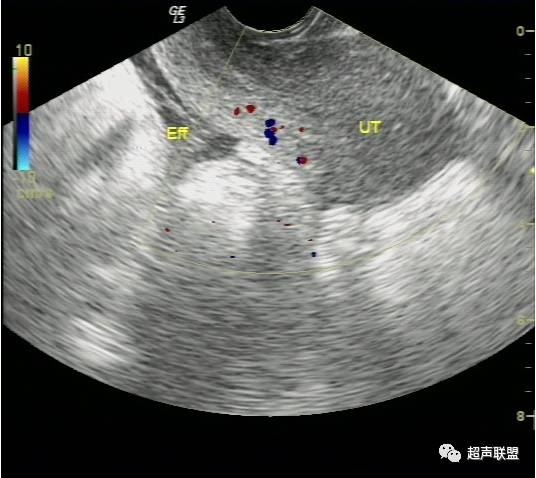

超声检查声像图特点:

(1)子宫增大或轻度增大,子宫内膜不同程度增厚,宫内未见妊娠囊。

(2)一侧附件区可探及不均质包块,包块形态欠规则,边界不清楚,回声紊乱。

(3)陶氏窝:可见多少不一不规则的液性暗区,暗区中有密集点状回声。

(4)卵巢囊肿破裂,患者过去多有囊肿病史,突发剧烈腹痛亦多有重击、及妇科检查等诱因。巧克力囊肿则多有痛经病史,由于其囊壁较厚一般不容易破裂,但当月经期出血量多时仍可以破裂。超声检查发现其子宫大小亦多正常,子宫内膜不厚,患者亦无停经史,尿HCG检查阴性。  总之,宫外孕破裂出血是妇产科最常见的急腹症之一。出血量大者,病情特别危急,需要立即做出诊断和鉴别诊断,以便采取适当而有效的治疗措施。对于一个临床主要表现为下腹剧烈疼痛,超声表现为附件或盆腔混合性包块,伴有盆腔甚至腹腔积液的妇科急症患者,检查者应该想到上述疾病。超声声像图注意观察子宫大小、子宫内膜厚度、盆腔积液的内部回声等。并尽可能详细询问月经史、性生活史及临床病史,结合尿或血HCG检查、血常规检查等,进行综合分析判断。随着超声仪技术的发展,阴道彩色多普勒检查的应用,宫外孕包块内滋养层血流的检测,将更有助于宫外孕破裂的诊断及鉴别诊断。

宫外孕破裂出血是妇产科最常见的急腹症之一。出血量大者,病情特别危急,需要立即作出诊断和鉴别诊断,以便采取适当而有效的治疗措施。对于一个临床主要表现为下腹剧痛,超声表现为:子宫轻度增大,子宫内膜不同程度增厚,宫内未见妊娠囊;一侧附件区可探及不均质包块,包块形态欠规则,边界不清楚,回声紊乱;陶氏窝可见多少不一不规则的液性暗区,暗区中有密集点状回声。盆腔甚至腹腔积液的妇产科急症患者。检查者应该想到上述疾病。并尽可能详细询问月经史、性生活史及临床病史,结合尿或血HCG检查、血常规检查等,进行综合分析判断。随着超声仪技术的发展,阴道彩色多普勒检查的应用,宫外孕包块内滋养层血流的检测,将更有助于宫外孕破裂的诊断及鉴别诊断。